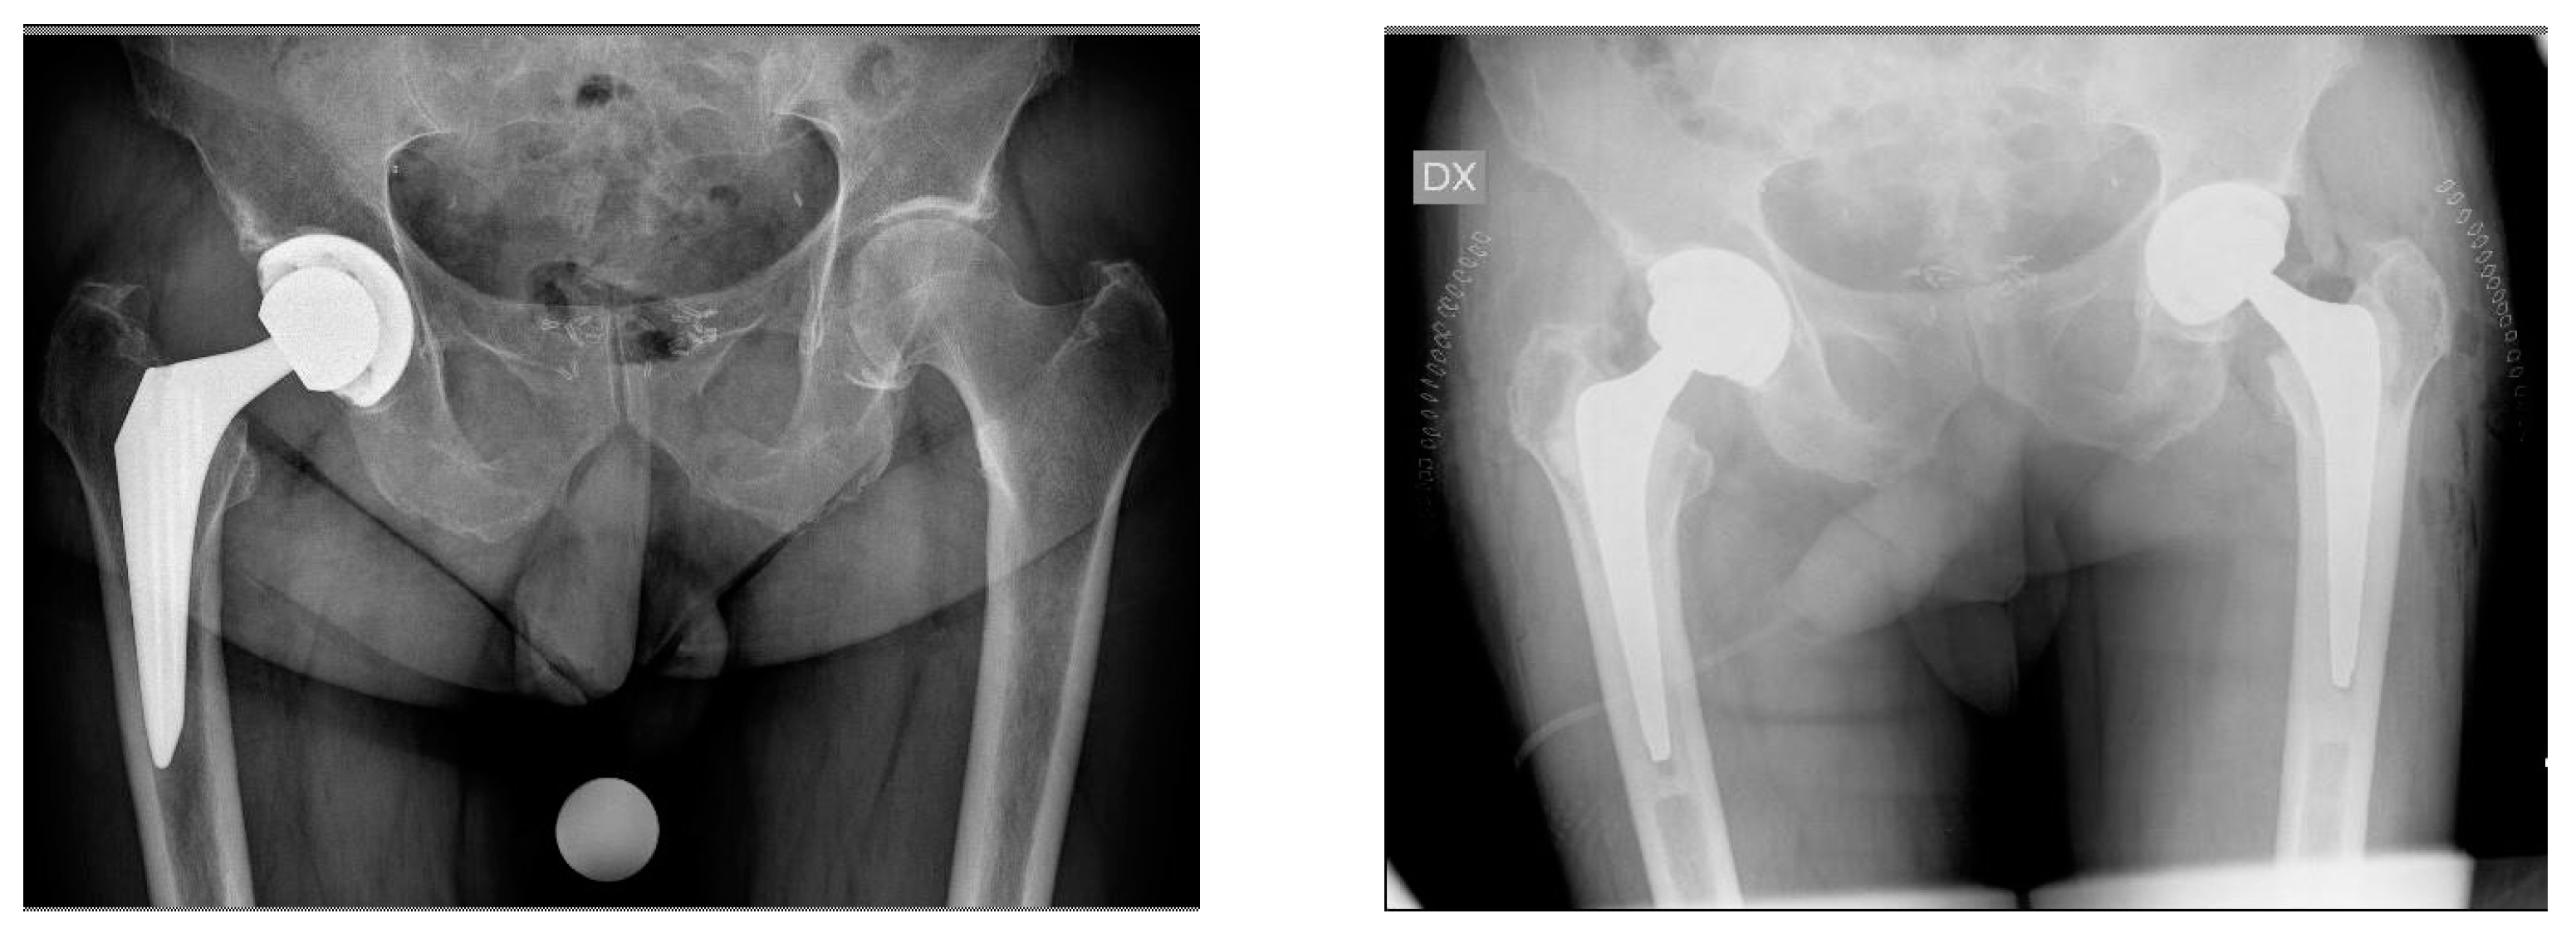

Revision of Failed Short Stems in Total Hip Arthroplasty

2.2. Surgical Technique